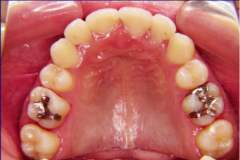

ステップ9. 矯正治療終了

ステップ8.装着撤去&保定治療開始